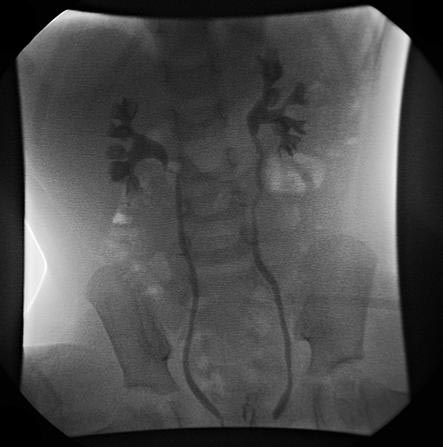

방광요관역류(Vesicoureteral reflux, VUR)는 소변이 방광에서 요관으로 거꾸로 흐르는 질환이다. 건강한 사람의 요관은 방광으로 비스듬히 들어가 밸브 역할을 하지만, VUR 환자는 이러한 메커니즘에 이상이 생겨 소변이 역류한다. 원인은 요관의 선천적 결함, 방광 압력 증가 등 다양하며, 증상은 무증상인 경우가 많지만 요로 감염, 발열, 배뇨통 등을 동반할 수 있다. 진단은 방광조영술, 초음파, 핵의학 검사 등을 통해 이루어지며, VUR의 중증도는 1~5등급으로 분류된다. 치료는 예방적 항생제 투여, 내시경 주입술, 수술적 치료 등이 있으며, 경과 관찰을 통해 자연 치유 여부를 확인하기도 한다.

4. 1. 배뇨성 방광 요도 조영술 (Voiding Cystourethrogram, VCUG)

배뇨성 방광 요도 조영술(VCUG)은 방광요관역류의 등급 분류 및 초기 검사에 선호되는 방법이다. 요로 감염이 있는 소아의 경우, 해부학적 원인을 배제하기 위해 VCUG와 복부 초음파 검사를 수행해야 한다.확정 진단은 배뇨 시 엑스레이를 통해 조영제의 역류 여부를 확인하는 배뇨성 방광 요도 조영술로 실시한다.[14][15] 늑골 척추각(CAV) 타진도 신우신염을 나타내므로 유효하다.[16]